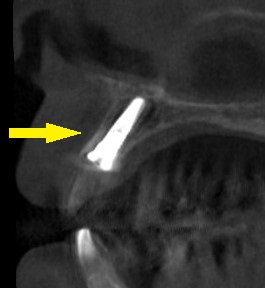

CTで見ると、歯の外側の骨は非常に薄くて、やや難しいのですが(下段左の写真)、抜歯してそのままそこにインプラントを埋入する、抜歯即時インプラント埋入術をお勧めしました。

下段右の写真が術後です。

外側に骨補填材も填入され、良好な状態で埋入できています。